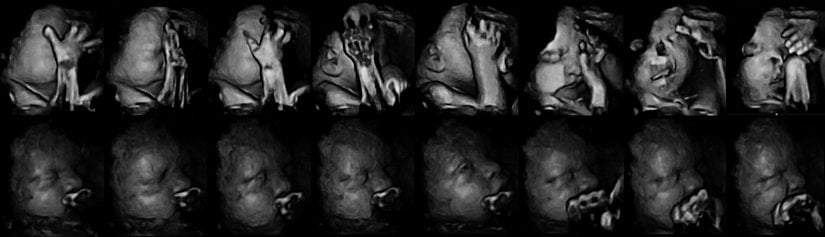

Aşağıda gördüğünüz, iki sıra bebek fotoğrafı. Bu fotoğrafları özel kılan şey, 4 boyutlu ultrason (3 boyutlu çekim + zaman) yöntemiyle kaydedilmiş olmaları. Ancak sadece bu da değil... Üstteki sıra, annesi sigara içen bir fetüse ait. Alttaki ise içmeyene...

İlk etapta çok fark görülemeyebilir. Ancak fotoğraf serisini soldan sağa doğru dikkatle takip edecek olursanız, üstteki bebeğin ağzını yüzünü hareket ettirdiğini ve eliyle yüzüne dokunmaya çalıştığını göreceksiniz. Alttakinin yüzü ise normal bir şekilde durmaktadır ve elleriyle yüzüne dokunma çabası yoktur.

"Ee, ne var bunda?" diyebilirsiniz... Sorun şu ki, bebekler hamileliğin erken evrelerinde yüzlerini buruşturmaya ve elleriyle yüzlerine dokunmaya meyillidirler. Bu normaldir. Ancak hamilelik süresi ilerledikçe, bu davranışlar giderek azalır ve bebek daha ziyade kollarına bacaklarına ve vücudunun geri kalanına dokunarak özellikle uzuvlarını tanımaya çalışır. Bunun nedeni, sinir sistemi ve beyni geliştikçe, uzuvlarını daha aktif olarak kullanmaya başlamasıdır. Yüzüne olan ilgisi azalır. Dahası, yüzünü de buruşturmayı bırakır.

Fakat Durham Üniversitesi tarafından yapılan yeni bir araştırmada, hamilelikte sigara içen annelerin yavrularında bu gelişim evrelerinin yavaşladığı gözlendi.[1] Yani üstteki seride, bebek aslında artık bırakmış olmasına rağmen yüzünü buruşturmaya devam ediyor ve yüzüne dokunmaya çalışıyor. Alttaki seride (sigara içmeyen anneni bebeği) ise normal gelişim görülüyor. Uzmanlar bu farklılığı sigaranın sinir sisteminin gelişimi üzerindeki yavaşlatıcı ve olumsuz etkiye bağlıyor.